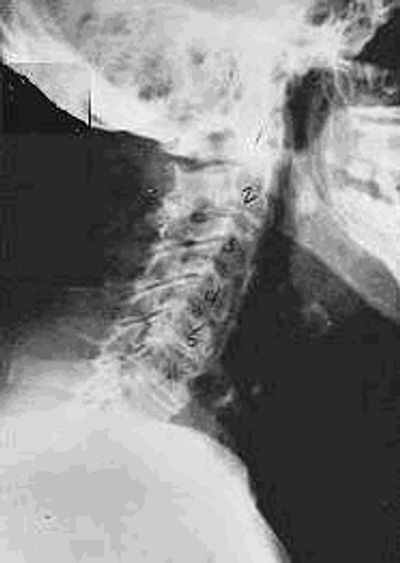

Phase Two Subluxation Degeneration

Phase two subluxation degeneration is normally seen in subluxations that have been present between 20 and 40 years. Subluxation Degeneration is a progressive process. Therefore, some of the same characteristics of the previous phase including a loss of normal curvature and position as well as an alteration in segmental motion continue into the second subluxation degeneration phase and continue to get worse. In addition, spines with Phase Two Subluxation Degeneration many times show a reduction in the patient's range of motion in that area. Patients begin having difficulty fully turning their heads to one side or the other or they are unable to turn their head without pain. Phase two subluxation degeneration x-rays begin to show changes to the bones. These changes include calcium deposits or buildup at certain levels of the spine. There are many common terms to describe these physiological changes including calcium spurs, “lipping”, osteophyte formation, osteoarthritis, OA and arthritis. Disc spaces between the affected vertebrae are noticeably narrower and may appear to be flattening out. Although most people with Phase Two Subluxation Degeneration may not exhibit any symptoms, some people may start to feel stiff or achy especially in the morning or after sitting for long periods of time. Chiropractic reconstructive care for patients in phase two ranges from 1.5 years to 2.5 years. Remember it took 20-40 years for your body to get to where it is currently, it will take time to heal properly. Again, if Phase Two Subluxation Degeneration is left uncorrected it will progress to the next phase.